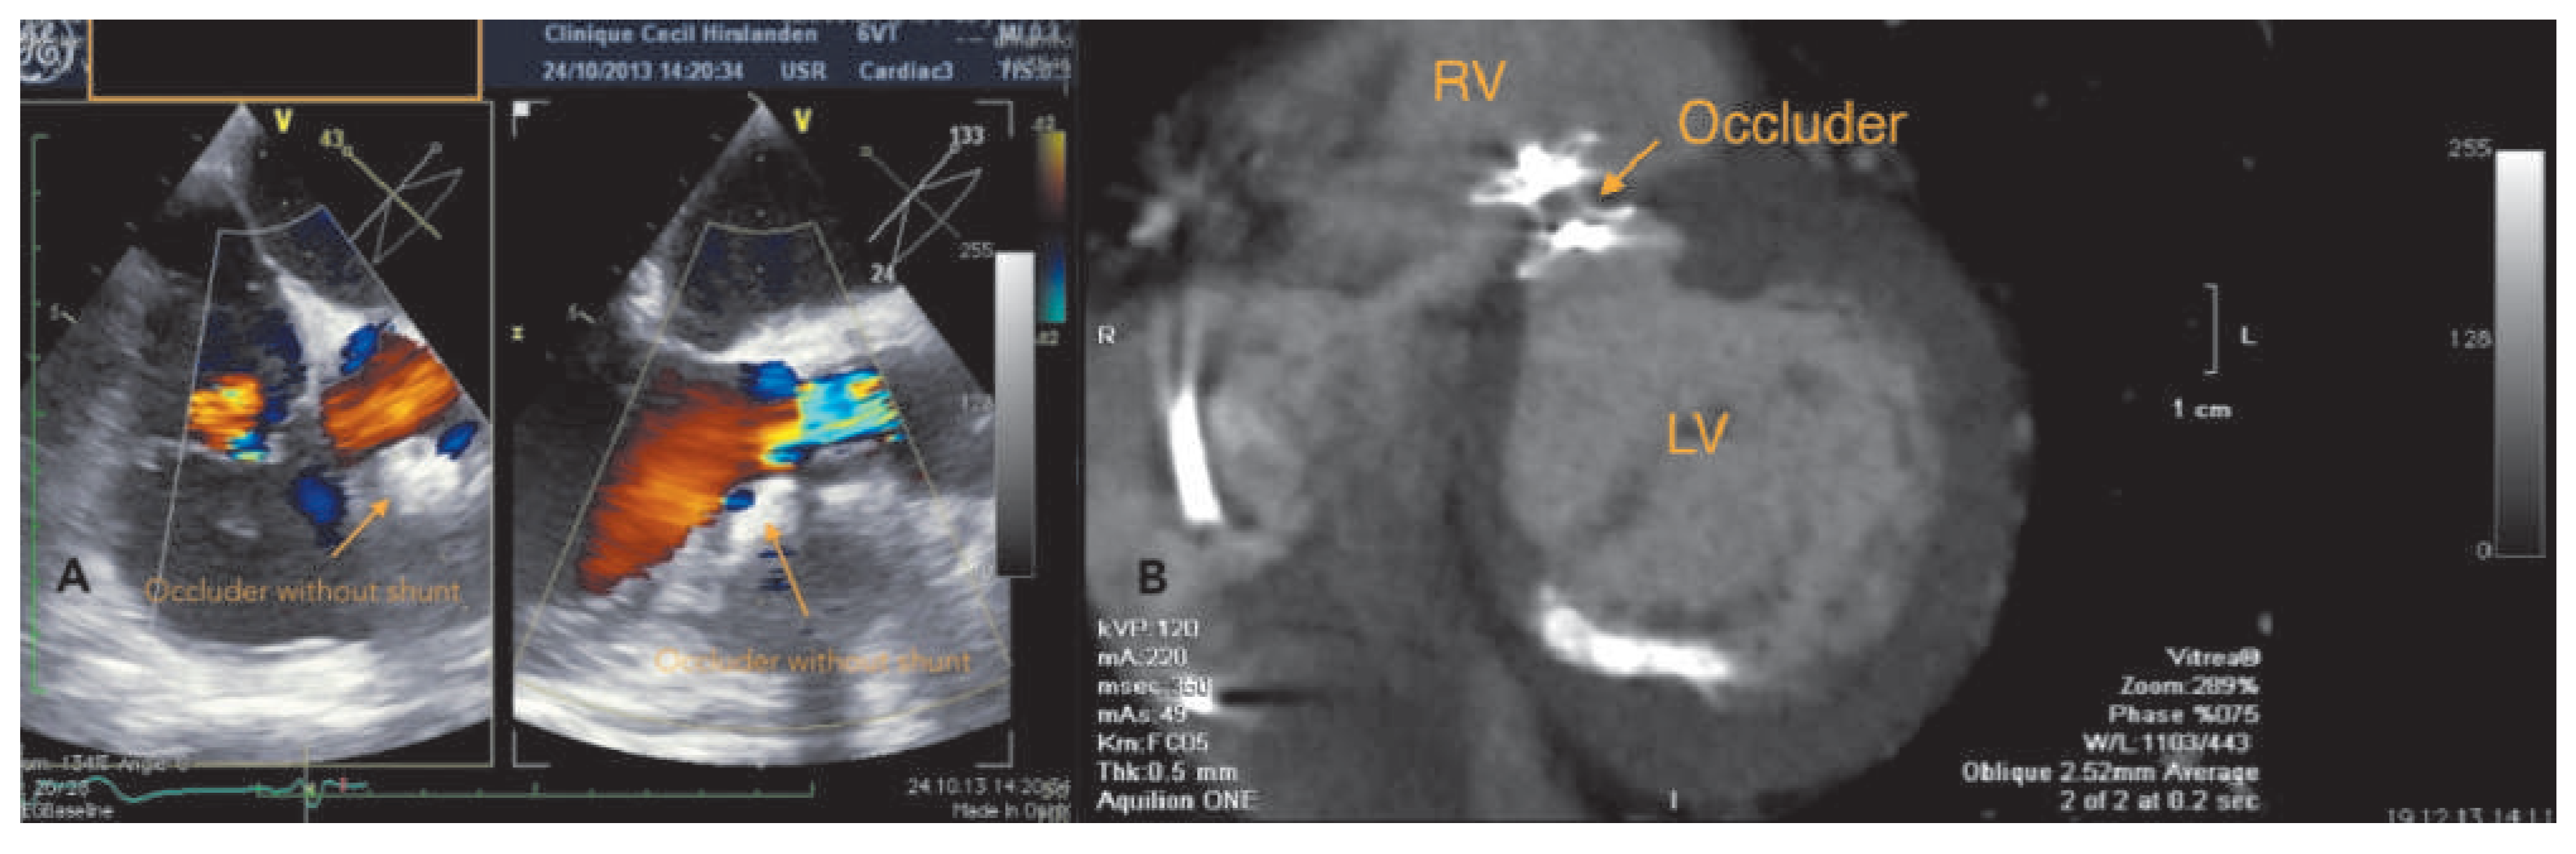

Case report